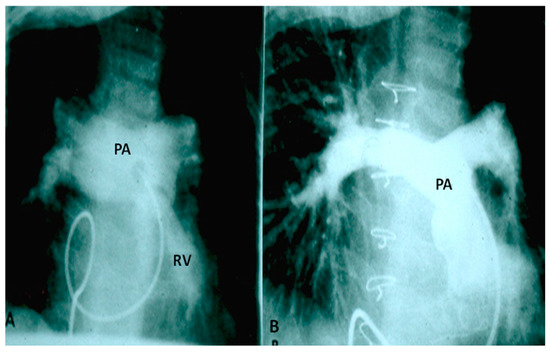

If the predominant obstruction is at the pulmonary valve level, though uncommon, balloon pulmonary valvuloplasty [12,13] to increase the pulmonary blood flow may be performed; balloon pulmonary valvuloplasty apart from increasing pulmonary blood flow, promotes growth and development of the pulmonary artery (Figure 2) and left ventricle so that a total surgical corrective procedure could be performed safely at a later time [12,13,14,15,16].

In premature babies two different palliative procedures were used as a bridge to total correction later. Balloon pulmonary valvuloplasty has been used in premature babies with TOF and significant arterial desaturaion as a bridge to total correction [17]. Similarly, deployment of a stent in RV outflow tract (Figure 3) may be used to promote growth of the pulmonary arteries and facilitate complete surgical correction at a later time [18].